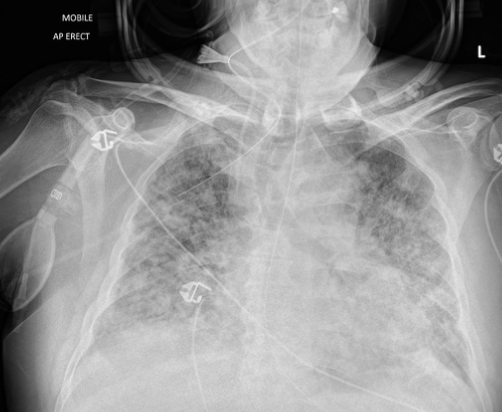

Pathology?

COPD - emphysema (abnormal permanent enlargement of the airspaces and alveolar wall destruction)

Pneumonia (alveolar air replaced with fluid, obscures lung markings)